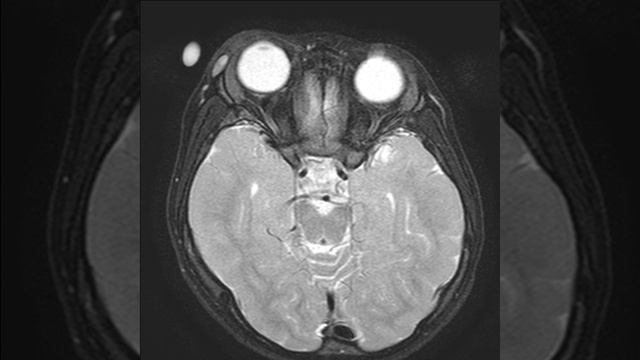

Атерома мрт

Атерома мрт 111 фото